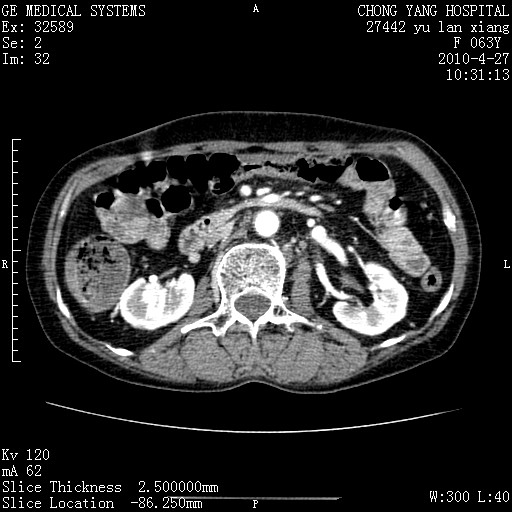

标题: CT26066:F63Y 上腹正中压痛半月,CA199:7400u/ml,MR示胰腺炎伴 [打印本页]

胰腺癌侵犯腹腔动脉干-分支、胃壁、左侧膈肌伴胰周及腹膜后淋巴结转移、胆囊切除术后。

胰腺癌侵犯腹腔动脉干-分支、胃壁、左侧膈肌伴胰周及腹膜后淋巴结转移、胆囊未显影。